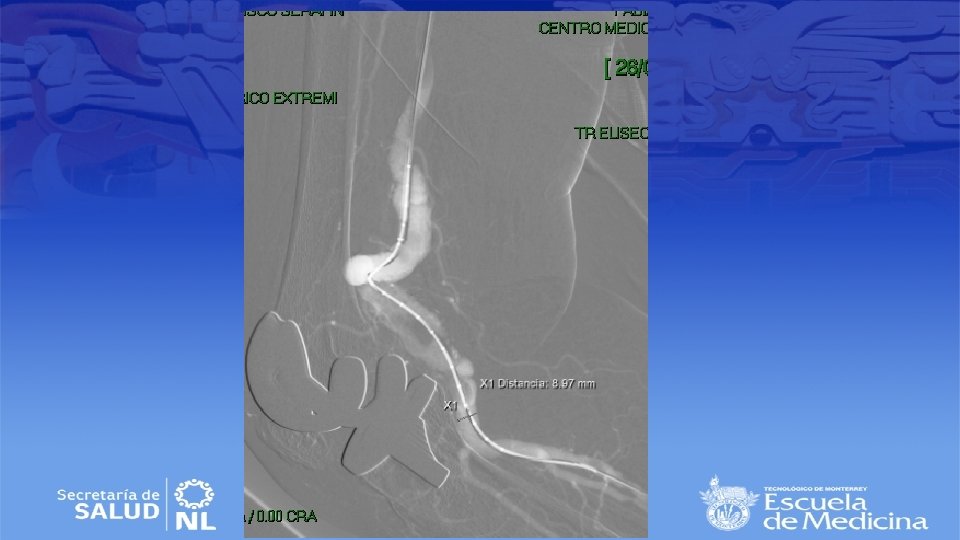

Diagnostico • Ultrasonido Doppler, Angiotac, angioresonancia • Arteriografía es mas apropiada para sintomatología aguda

Cirugía de emergencia • Establecer viabilidad de la extremidad (buscar deficiencia motora o sensitiva) • Sin daño se inicia anticoagulación sistémica y se realiza angiografía en busca de algún vaso viable para bypass. • Si no se encuentran se realiza trombolisis dirigida • Si se encuentra daño el bypass sigue siendo el mejor tratamiento • Si no hay vaso viable se realizara trombectomía tibial

Cirugía endovascular • Para pacientes con alto riesgo quirúrgico • Deben de tener al menos 2 cm de arteria proximal y distal sin patología para anclar la endoprótesis • Se repite la angiografía durante el procedimiento para selección de la endoprótesis correcta • Debe de ser 10 a 15% mas grande que el diámetro del vaso